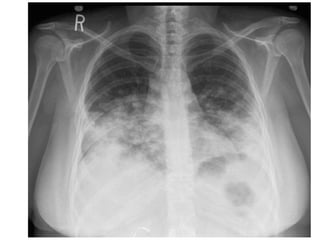

Blastomicosis: Rx de tórax

• Infiltrados focales alveolares en

lóbulos superiores, a menudo de

aspecto nodular

• Cavitaciones frecuentes (1/3 de los

casos)

• El 15 % masa que se confunde con Ca

• Patron micronodular < del 1%.

• Adenopatías y calcificaciones raras.

Blastomicosis: Rx detórax • Infiltrados focales alveolares en lóbulos superiores, a menudo de aspecto nodular • Cavitaciones frecuentes (1/3 de los casos) • El 15 % masa que se confunde con Ca • Patron micronodular < del 1%. • Adenopatías y calcificaciones raras.